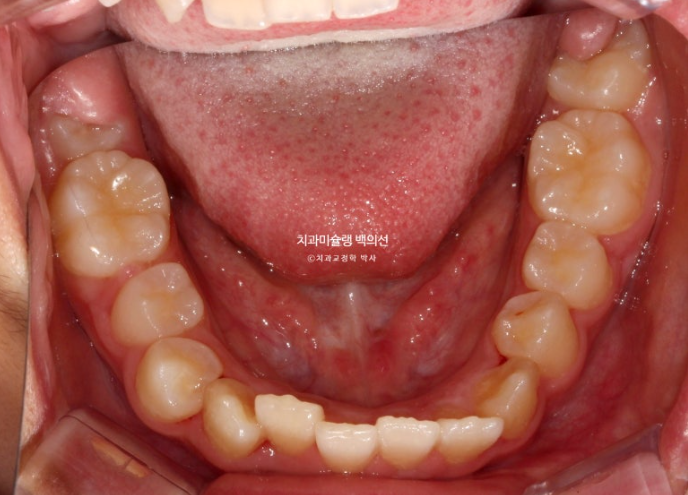

그 사이 하나 남아있던 유치가 빠지고 완전한 영구치열에 접어들었습니다.

24.09

교합과 아래배열은 완벽하게 유지되고 있습니다.